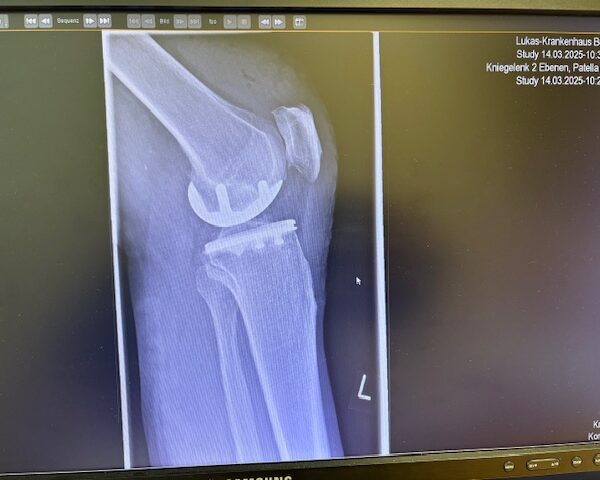

Ο ακτινολογικός έλεγχος (ακτινογραφίες/μαγνητική τομογραφία) ανέδειξε προχωρημένη οστεοαρθρίτιδα του έσω κονδύλου, με πλήρη διατήρηση του έξω διαμερίσματος και της επιγονατιδομηριαίας άρθρωσης. Με βάση αυτά τα ευρήματα, ο ασθενής ήταν ιδανικός υποψήφιος για μερική (μονοκονδυλική) αρθροπλαστική γόνατος.

Η επέμβαση πραγματοποιήθηκε με ελάχιστα επεμβατική προσπέλαση και τοποθέτηση πρόθεσης μόνο στον έσω μηροκνημιαίο διαμέρισμα του γόνατος.

Η ακριβής προσαρμογή του εμφυτεύματος επιβεβαιώθηκε διεγχειρητικά, εξασφαλίζοντας σταθερότητα και φυσική κίνηση της άρθρωσης.

Στον ασθενή τα εμφυτεύματα που χρησιμοποιήθηκαν είναι της εταιρείας Zimmer-Biomet Persona Μηριαίο μέγεθος 6, κνημιαίο μέγεθος Η και ενθέμα (inlay) Η li. 8mm.